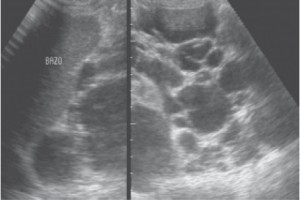

Diplomados en Ultrasonografía